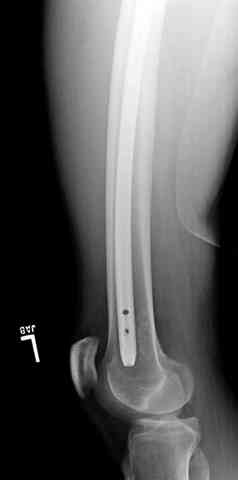

Закрытый интрамедуллярный interlocking остеосинтез гвоздем с антибиотиковым цементным покрытием немедленно.

Для интрамедуллярного остеосинтеза это идеальная линия перелома, лишь бы вверху и внизу бедра оставалось см по 4-5.

Пуля от ПМ - очевидно, что ранение было т.н. низкоэнегетическим, что подтверждается в том числе спокойным состоянием мягких тканей в этом, уже отсроченном периоде.

Однозначно, огнестрельные переломы стоит стабилизировать АНФ в максимально ранние сроки после получения ранения. Так же при ПХО или повторной ХО требуется фасциотомия. Эти две манипуляции приводят к улучшению паравульнарного кровотока и уменьшают вероятность развития вторичных осложнений. Дождавшись закрытия ран и при полной уверенности в отсутствии гнойных осложнений можно поднимать вопрос о конверсии наружного остеосинтеза на внутренний. Судя по снимку, пуля пистолетная, перелом не носит многооскольчатый характер, что дает основание полагать, что невысокая энергия ранения подразумевает невысокую вероятность вторичных осложнений и возможность внутреннего остеосинтеза. Конечно, БИОС в а\б муфте предпочтительнее ввиду щадящего отношения к кровообращению в заинтересованной области, но лучшая методика та, которой хорошо владеет хирург.

Небольшие входные пулевые раны до 1 см (см. на снимке) закрываются в течение нескольких дней самостоятельно даже без обработки. Раны более 3 см также не нуждаются в специальной обработке, и для самостоятельного закрытия ран бывает достаточной обычная обработка стенок раны "кюретажем".

Характерным признаком травмы с низкой кинетической энергией является отсутствие "мультифрагментации и кавитации", и поэтому в данном случае лечение можно проводить любым доступным методом.

Для фиксации огнестрельных переломов бедра и длинных костей предпочтение отдаем интрамедуллярному методу фиксации, о котором еще в 1993 году написали Bergman M. Tornetta P. Kerina M. Sandhu H. Simon G. Deysine G. Journal of Trauma. [JC:kaf] 34(6):783-5

1 Проксимальный перелом бедра, антеградный гвоздь